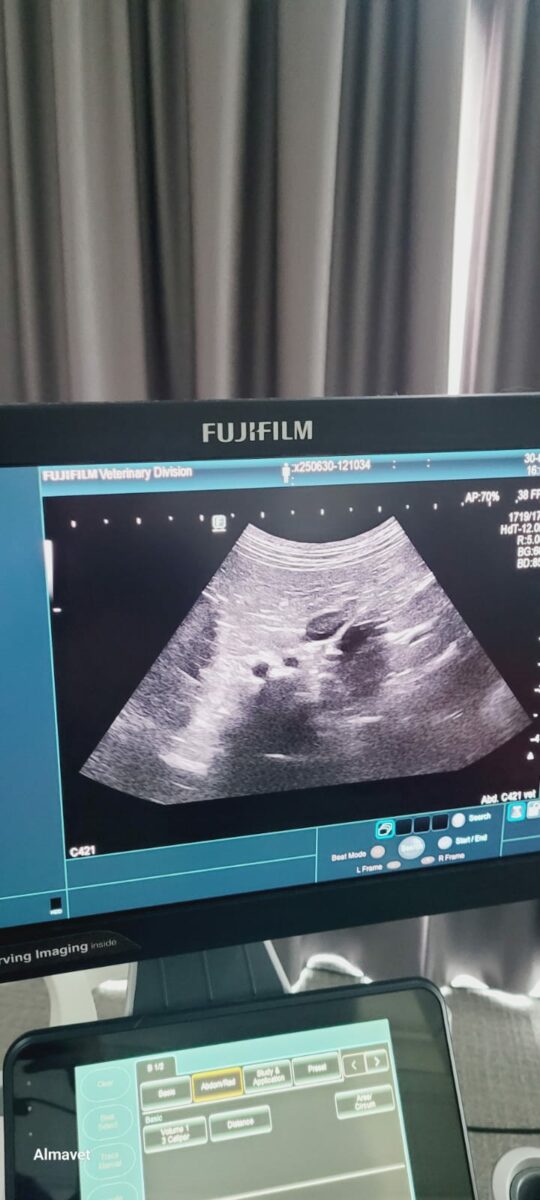

W czerwcu 2025 lek. wet. Monika Zawolik wzięła udział w 1 części Europejskiego kursu ultrasonografii małych zwierzat w Luxemburgu. Pod okiem wybitnych specjalistów w tej dziedzinie ćwiczyła przede wszystkim praktykę! Wspaniały czas z innymi lekarzami , którzy chętnie dzielili się doświadczeniem i przypadkami klinicznymi .